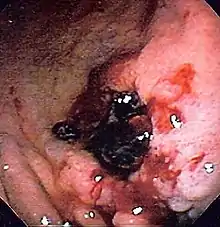

![]() Endoscopic still of esophageal ulcers seen after banding of esophageal varices, at time of esophagogastroduodenoscopy | |

- Treatment (banding/sclerotherapy) of esophageal varices